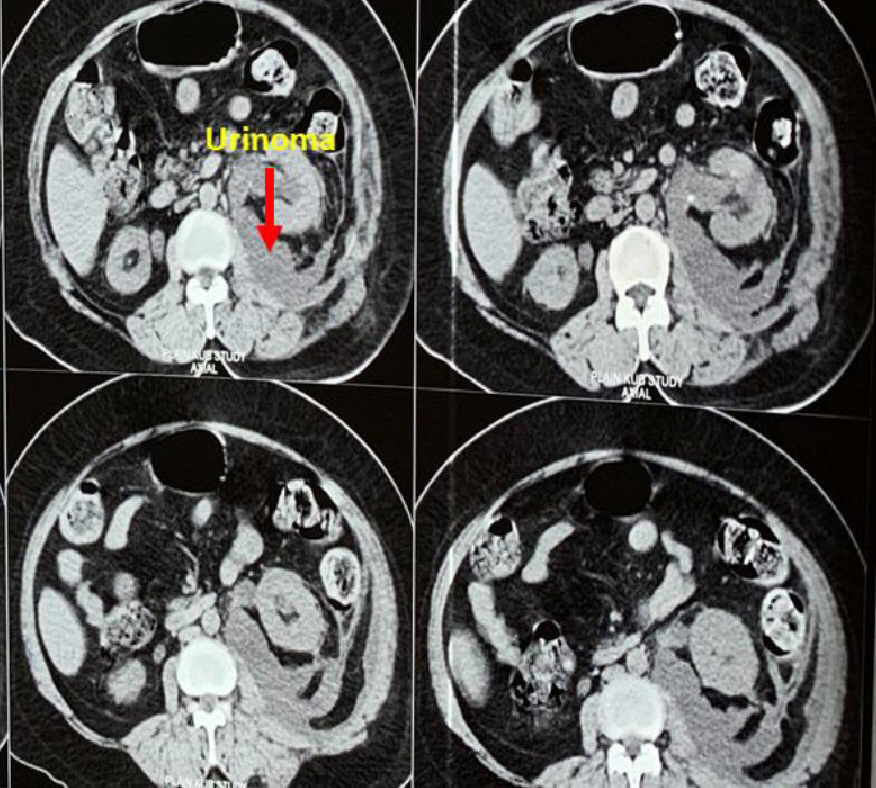

Management of Ureteric Avulsion During Ureteroscopy: Our Experience in A Case SeriesUreterorenoscopy (URS) is usually a safe procedure without any complications. Ureteric avulsion is the most dreaded complication of URS. Most urologists do not have experience in management of ureteric avulsion injuries. Inappropriate management can lead to nephrectomy.